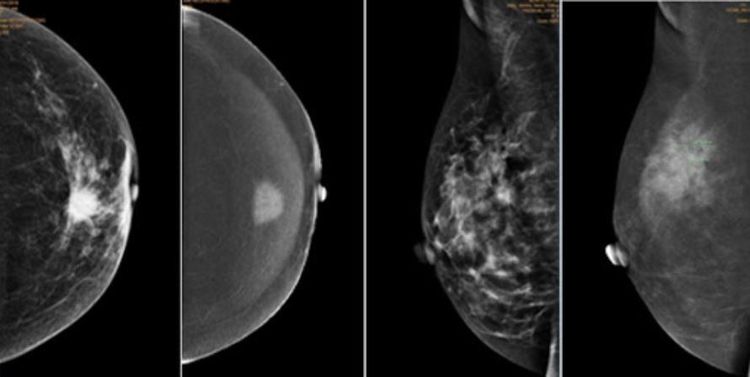

2. Kiểm tra ngực và chụp quang tuyến vú

Ung thư vú là một trong những căn bệnh ung thư thường gặp nhất ở nữ giới. Do đó, việc kiểm tra vú thường xuyên là một điều vô cùng quan trọng nhằm phát hiện ra ung thư từ sớm và có biện pháp điều trị kịp thời. Đặc biệt, những phụ nữ có độ tuổi từ 40 trở lên nên tự kiểm tra vú định kỳ tại nhà, hoặc đi khám vú 1 lần/năm.

Theo Hiệp hội Ung thư Hoa Kỳ khuyến cáo rằng, phụ nữ sau 40 tuổi cũng nên thực hiện chụp X quang tuyến vú để sàng lọc ung thư vú. Ở người Việt Nam do mô vú đặc nên xét nghiệm sàng lọc thường phối hợp giữa X quang tuyến vú và siêu âm vú. Các xét nghiệm có thể được thực hiện định kỳ mỗi năm một lần, hoặc cách năm.

Chụp X-quang tuyến vú giúp chẩn đoán những biểu hiện bất thườn của tuyến vú